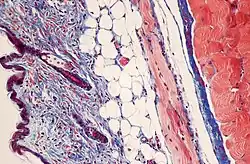

Коллагеновый гастрит, окраска трихромом Массона